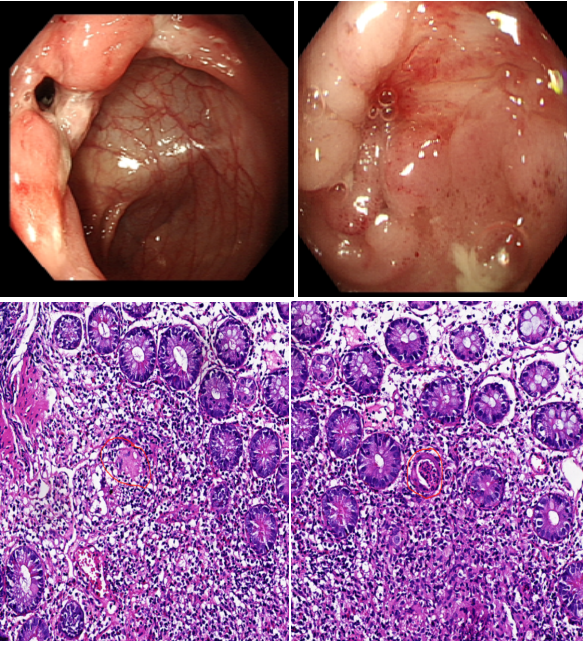

消化內(nèi)科二區(qū)通訊員譚思、李霞報道:近日,一位骨瘦如柴24歲小伙慕名來到衡陽市中心醫(yī)院消化內(nèi)科二區(qū)就診。該患者因腹瀉1年余,且伴有排便后肛周疼痛不適,輾轉(zhuǎn)多家醫(yī)院治療果,整個人變得郁郁寡歡。接診時,患者體重僅有42KG,BMI只有14肛周有一1厘米左右的,有觸痛。何小梅醫(yī)生立即給予安排小腸CTE及腸鏡等檢查,發(fā)現(xiàn)腸道有節(jié)段性的潰瘍病變。病區(qū)主任舒寶蓮綜合臨床表現(xiàn)、生化指標(biāo)、小腸CTE、腸鏡及病理結(jié)果,診斷患者“克羅恩病肛周病變”。在對患者疾病的活動程度進(jìn)行評估,基于患者年齡以及伴有肛周膿腫2項(xiàng)高危因素綜合考慮,給與患者使用生物制劑“英夫利西單抗”對癥治療。目前,患者腹瀉及肛周疼痛有明顯的好轉(zhuǎn),患者及母親對診療效果非常滿意。出院時,患者充滿感謝地對醫(yī)務(wù)人員說:“醫(yī)生很快就找到了病因,又通過個體化的營養(yǎng)治療增加了我的體重,醫(yī)務(wù)人員還耐心地對我進(jìn)行健康宣教與心理疏導(dǎo),謝謝你們解決了困擾我生活的大問題。

克羅恩?。?/span>CD):是一種病因尚不明確的胃腸道慢性炎性肉芽腫性疾病。病變多見于末端回腸和臨近結(jié)腸,但從口腔至肛門各段消化道均可受累,呈節(jié)段性或跳躍式分布。臨床上以腹痛、腹瀉、體重下降腹塊、瘺管形成、肛周病變及腸梗阻為特點(diǎn),可伴有發(fā)熱的全身表現(xiàn)以及關(guān)節(jié)、皮膚、眼、口腔粘膜等腸外損害。發(fā)病年齡多在15-30歲,但首次發(fā)作可出現(xiàn)在任何年齡組。本病有終生復(fù)發(fā)傾向,重癥或者遷延不愈。預(yù)后不良??捎心c梗阻、腹腔膿腫、消化道出血及結(jié)癌變等并發(fā)癥發(fā)生。

克羅恩病的診斷需結(jié)合臨床表現(xiàn)、實(shí)驗(yàn)室指標(biāo)、影像學(xué)(小腸CTE)、腸鏡及病理。